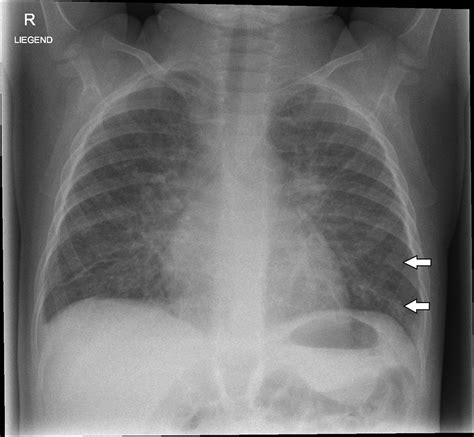

Kerley B lines are short, horizontal, linear opacities seen on chest X-rays. They are typically found in the peripheral lung fields, particularly in the costophrenic angles. These lines are named after Peter Kerley, the radiologist who first described them. Kerley B lines are often associated with interstitial edema, which is the accumulation of fluid in the interstitial spaces of the lungs.

• Identify the Location: Kerley B lines are usually found in the peripheral lung fields, particularly in the costophrenic angles.

• Assess the Pattern: Look for short, horizontal, linear opacities. These lines are typically less than 1 cm in length and are often seen in clusters.

• Evaluate the Context: Consider the clinical context and other findings on the CXR. Kerley B lines are often accompanied by other signs of pulmonary edema, such as alveolar opacities and pleural effusions.